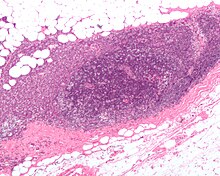

Une fois repéré, le chirurgien procède à une biopsie/exérèse du ou des ganglions sentinelles. Ce prélèvement est envoyé au médecin anatomopathologiste qui souvent, pour guider le reste de la chirurgie, doit rendre des résultats d'orientation diagnostique dans les 30 minutes dans le cadre de ce qu'on appelle une analyse extemporanée. Le but étant de déterminer la présence ou non de cellules cancéreuses.

D'autres analyses anathomopathologiques plus longues seront dans tous les cas effectuées pour être certain du statut (sain ou pathologique) ganglionnaire.